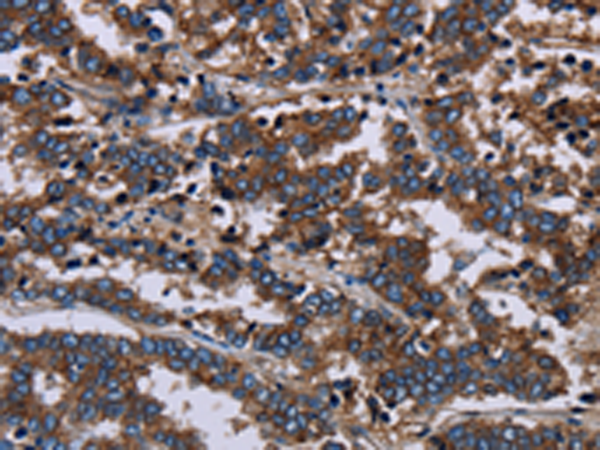

分类: 科研抗体货号: P08484别名: LRDD; PIDD应用: IHC反应种属: Human

分类: 科研抗体货号: P08472别名: CT32; LDH3; LDHX应用: WB,IHC反应种属: Human